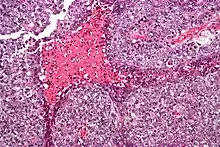

Micrograph of an embryonal carcinoma showing its typical features – prominent nucleoli, marked nuclear atypia, necrosis, and nuclear overlap. H&E stain. | |

The microscopic features include: indistinct cell borders, mitoses, a variable architecture (tubulopapillary, glandular, solid, embryoid bodies – ball of cells surrounded by empty space on three sides), nuclear overlap, and necrosis.